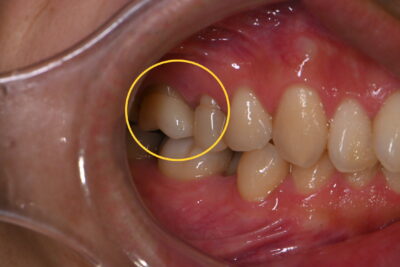

神経保護まで終わりその後、歯の周りの形を削り型取りしジルコニアクラウンを入れた方になります?

処置前 ↓ ↓ ↓

綺麗に被せ物が入りましたがこの方は歯肉退縮を起こしてるため、入った後から歯茎が下がらないようによく経過観察しなければなりません。電動歯ブラシを今使用してるので動かし方や当て方を次回確認していきます?